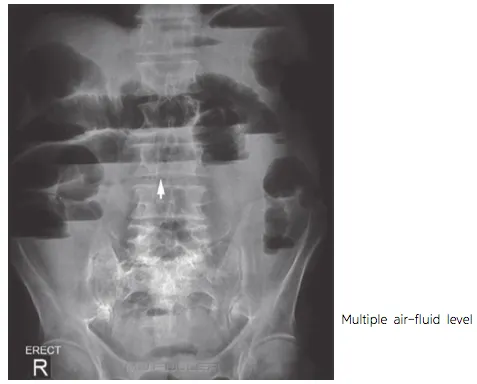

D2. Imaging

(1) Simple film : Abd S/E, Chest PA, Lat. decubitus (greatest volue : free air detection)